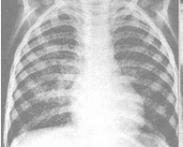

妊娠合并肺結核

• 妊娠合并肺結核

628健康網為您分享有關妊娠合并肺結核的癥狀,妊娠合并肺結核的治療方法,妊娠合并肺結核的預防知識,妊娠合并肺結核的癥狀...